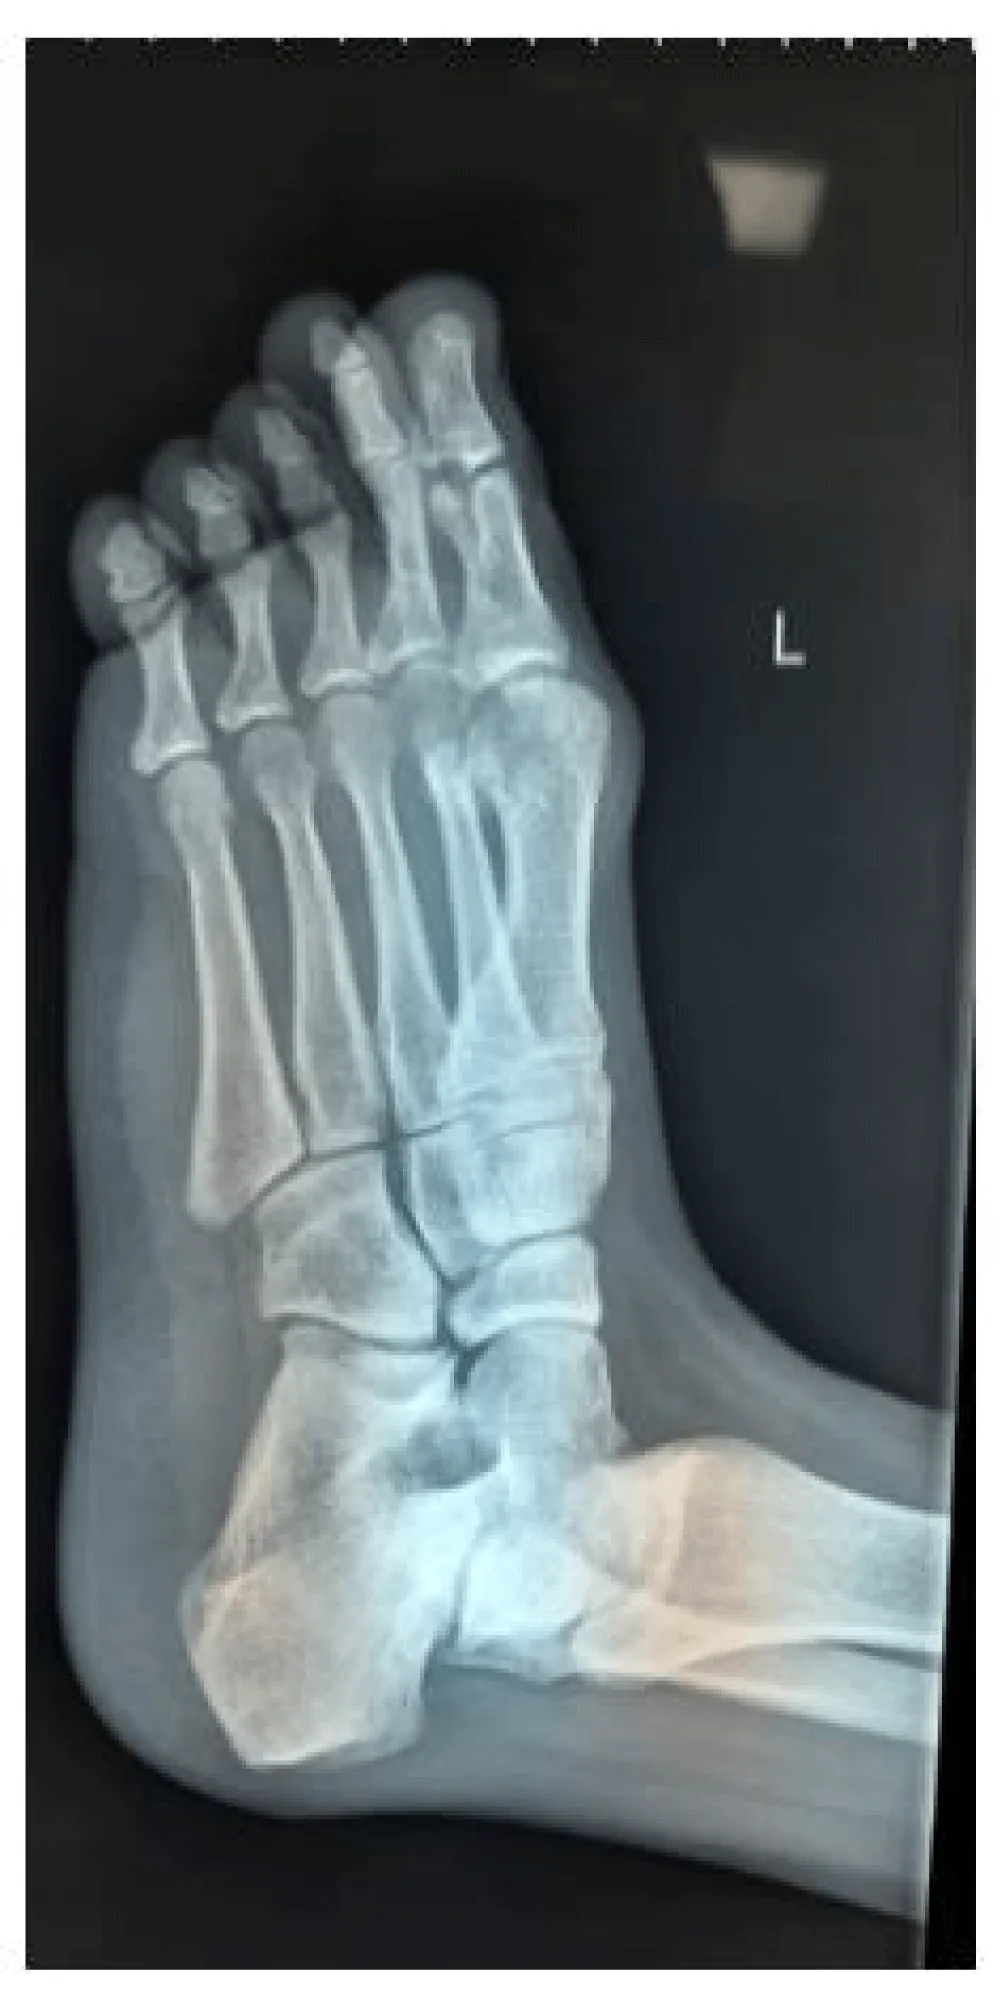

A 32-year-old male patient with no medical co-morbidity was brought to the emergency department of our hospital late at night following a motor vehicle accident with main complaints of trauma to the left foot and ankle, which was swollen with deformity of the lesser toes with associated painful attempted movements. Distal foot vascularity was intact with intact neurology. The medial aspect of the ankle was swollen with tenderness around the medial malleolus. Radiographs of the injured foot and ankle revealed dorsoradial dislocation of the lesser four toes at MTP joints with a unicortical crack seen in the ipsilateral medial malleolus (Figure 1).